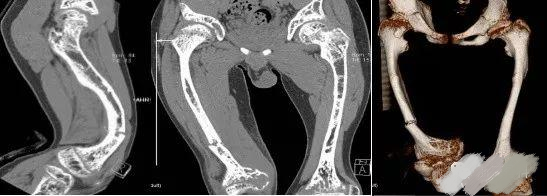

OI标志性特征是骨质脆弱反复骨折, 典型骨骼X线表现(见图二);成骨不全症的临床表现不仅限于骨骼,还常常累及其他结缔组织如眼、耳、皮肤、牙齿等(见图三)。根据临床表型, 澳洲悉尼大学的Sillence教授将OI 分成至Ⅰ-Ⅳ型[7]: Ⅰ型病情最轻, 最常见; Ⅱ最重, 通常围产期致死; Ⅲ型是存活者中最严重的, 常常身材矮小, 呈进行性骨骼畸形; Ⅳ型严重度介于Ⅰ型与Ⅲ型之间。近期发现的Ⅴ型OI 具有肥厚性骨痂、桡骨头脱位、前臂骨间膜钙化、桡骨干骺端下密集骺线等独特临床表现(见图四)。

图二:成骨不全症典型的X线表现

a.股骨干侧位片显示双侧非对称的股骨前弓弯曲愈合中的骨折(实心箭头)和已经愈合的骨折(空心箭头)

b. 胫骨侧位片显示双侧胫骨向前弯曲以及骨折愈合的不同阶段:早期愈合(实心箭头),进行性愈合中(空心箭头),已经愈合(三角);双侧胫骨呈现铅笔样畸形,尤其是腓骨及蜂巢状髓腔,特别是胫骨远端。

c. 骨盆平片显示严重的股骨近端髋内翻畸形以及基本完全愈合的转子下骨折;骨折愈合一般从内侧(压应力侧)开始,而骨折不愈合通常发生外侧表面(张应力侧);

d. 胸腰段脊柱侧位片显示椎体及附件广泛骨质疏松,椎体呈双凹征(空心箭头),扁平椎(实心箭头)以及各种程度的椎体前方楔形变,总的来说成骨不全患者脊柱骨骼改变与生长激素替代治疗的骨骼改变表现非常类似,骨硬化与骨吸收相互交错;

e. 肱骨的前后位片可以看到多条横形的硬化带,代表的是双磷酸盐治疗周期;同时还可以看到向外拉长、变薄变细的锁骨和肋骨以及增宽的肋间隙;

g.皮肤松弛症的X线片表现有时与成骨不全的比较类似,股骨干前后位片显示已经愈合的股骨干骨折;

h.上肢的前后位片显示双侧的尺骨向外侧弯曲成角,肱骨远端向内侧成角(实心箭头),同时伴有桡骨小头脱位(空心箭头)。